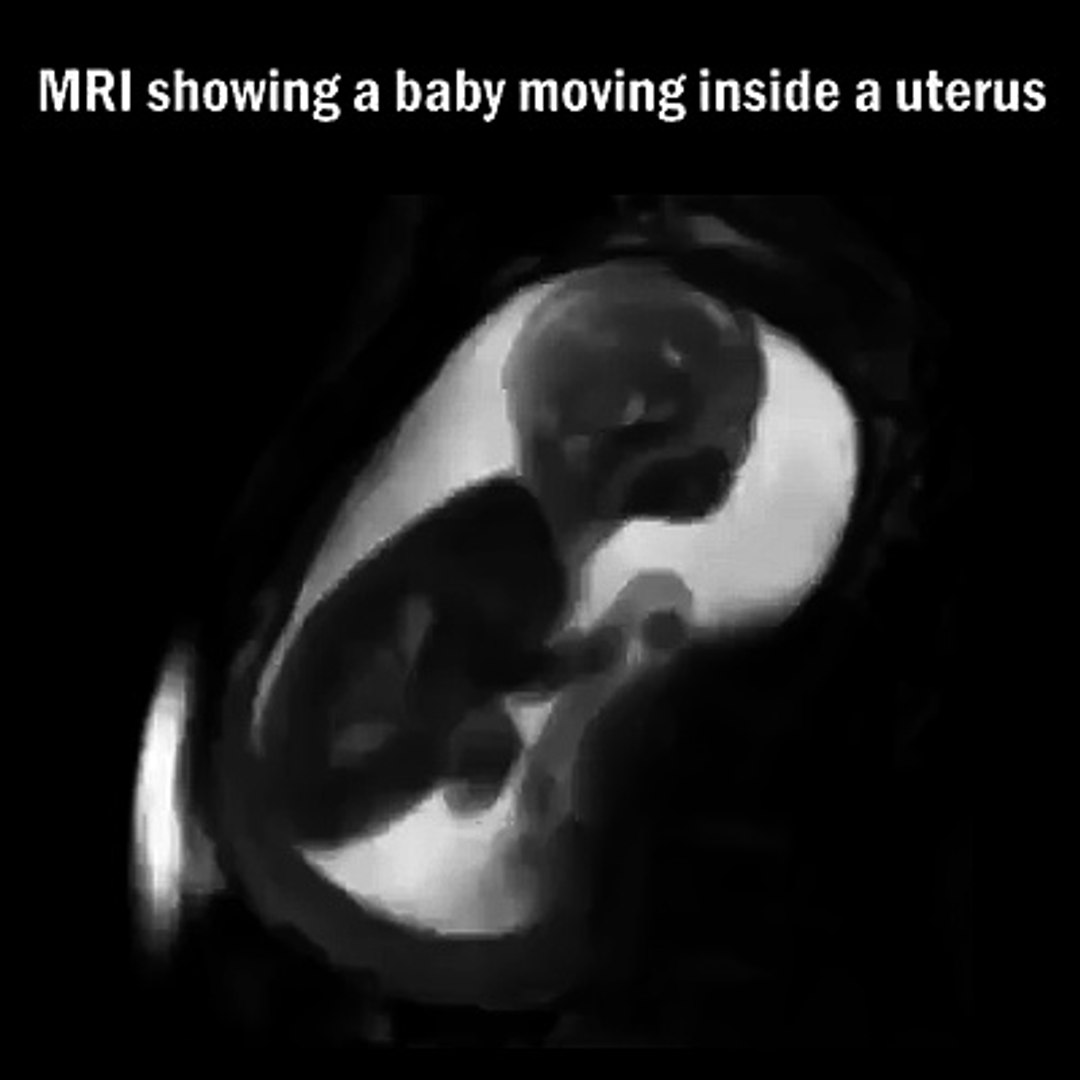

Early Pregnancy Pregnant Mri

Si vraiment, tu as trop peur, demande au doc qui sera là de te rassurer ou de te donner un tablier de plombEn ayant recours à l'IRM, une femme enceinte peut voir son bébé à l'intérieur de son ventre, en ayant une idée claire sur sa déglutition, ses étirements et ses mouvements Dans le cas des jumeaux, les images de l'IRM rendent compte du rapport entre les deux bébés et peut même les montrer entre de se débattreAlgodystrophie de la hanche chez la femme enceinte Des douleurs de hanche apparaissent parfois de manière unilatérale, parfois de manière bilatérale en fin de grossesse , généralement au troisième trimestre Cette pathologie est assez rare, mais non exceptionnelle, et souvent mal connue à la fois des gynécologues, mais aussi de nos